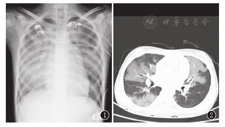

73例患儿中,66例肺出血后2 h内完善床旁胸片或CT。61例胸部平片提示双肺透过度减低、多发渗出性病变(其中4例并胸腔积液,2例并气胸,5例高密度斑片影以左肺为主,4例高密度斑片影以右肺为主)。5例双肺纹理增强。图1为1例暴发性心肌炎并肺出血胸片,图2为相同患者的CT。